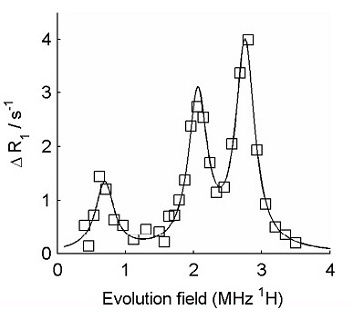

FFC-NMR relaxometry on normal cartilage (squares) and cartilage from patient with osteoarthritis (circles). The difference between the two is clear. The data were further analysed by subtracting the "background" from the curves, in order to isolate the quadrupole peaks, as shown below.

The amplitude of the quadrupolar peaks is clearly reduced in the osteoarthritic cartilage.

Isolated (background-subtracted) quadrupole peaks obtained using FFC-NMR relaxometry on normal cartilage

Isolated (background-subtracted) quadrupole peaks obtained using FFC-NMR relaxometry on cartilage from an osteoarthritic joint These preliminary results indicate that there appears to be significant potential for the detection of osteoarthritic changes in joints using FFC methods. Further research is being carried out in our labs, funded by a grant from Arthritis Research UK .